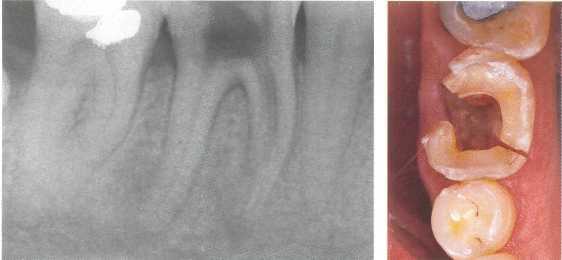

Рис. 705. Вертикальный перелом корня.

Нижний первый моляр с вертикальным переломом медиального корня через неделю после инструментальной обработки канала. Пациент жалуется лишь на слабую боль. На рентгенограмме однозначно определяется продольный перелом медиального корня. Справа: перелом захватывает также и коронку. Медиальный сегмент подвижен.